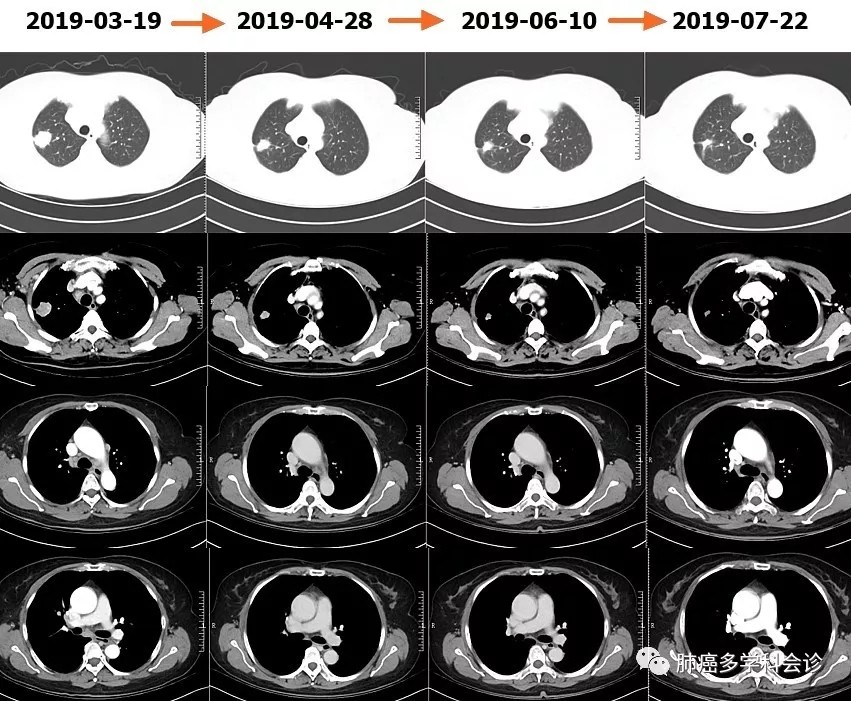

于2019-3-20 ~ 2019-7-3期间行 "培美曲塞+卡铂"化疗6周期。胸部肿瘤逐步缩小。

以下是化疗前后和期间肿瘤的变化: